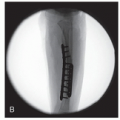

Use fluoroscopy to identify medullary canal ulna

Choose wire diameter that will fill 50%-75% of the ulna medullary canal

Identify entry site olecranon apophysis (Figure 13.6)

Medullary canal usually thinner than expected

Choose smaller diameter smooth wire to fit full-length ulna